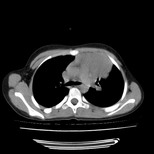

经过胸部穿刺活检为支原体感染。以下示抗支原体感染30天后所见,病灶明显缩小,临床症状消失: